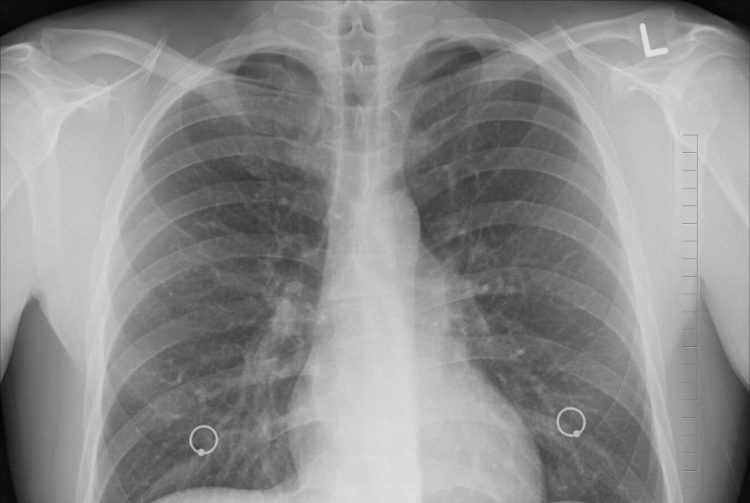

La comparsa dei sintomi nei primi sei casi risale al periodo compreso tra il 18 e il 22 agosto. “Ciò che questi pazienti hanno in comune è la severità del quadro respiratorio, determinata da una polmonite interstiziale bilaterale – spiega Luis Medina Ruiz, ministro della Salute della Provincia del Tucumàn -. Un quadro simile a quello di Covid-19, confermato anche dalle radiografie toraciche. Ma evidentemente di altra origine: l’infezione da Sars-CoV-2 è stata infatti esclusa in tutti i casi finora rilevati”. Questa come altre possibili 25 cause virali o batteriche. Da qui la scelta di inviare i campioni dei pazienti al Malbran Institute di Buenos Aires – centro di riferimento nazionale per le malattie infettive – per compiere ulteriori indagini.